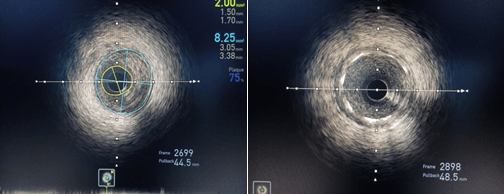

術(shù)前IVUS示最小管腔面積2.00mm2;術(shù)后IVUS示最小支架面積7.61mm2